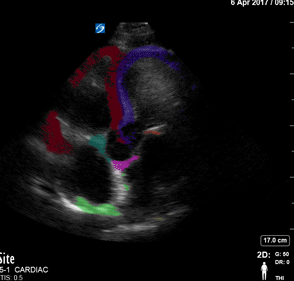

Colorized Atlas - Apical 4 - Colorized - Complex

Apical 4 View Red: Right Ventricle, Green: Right Atrium, Blue: Left Ventricle, Yellow: Left atrium. Pink: Mitral valve. Teal: Tricuspid Valve. Images: Dr. Lindsay Davis, Dr. Hannah Kopinski. Image Editing: Michael Amador and Dr. Matthew Riscinti